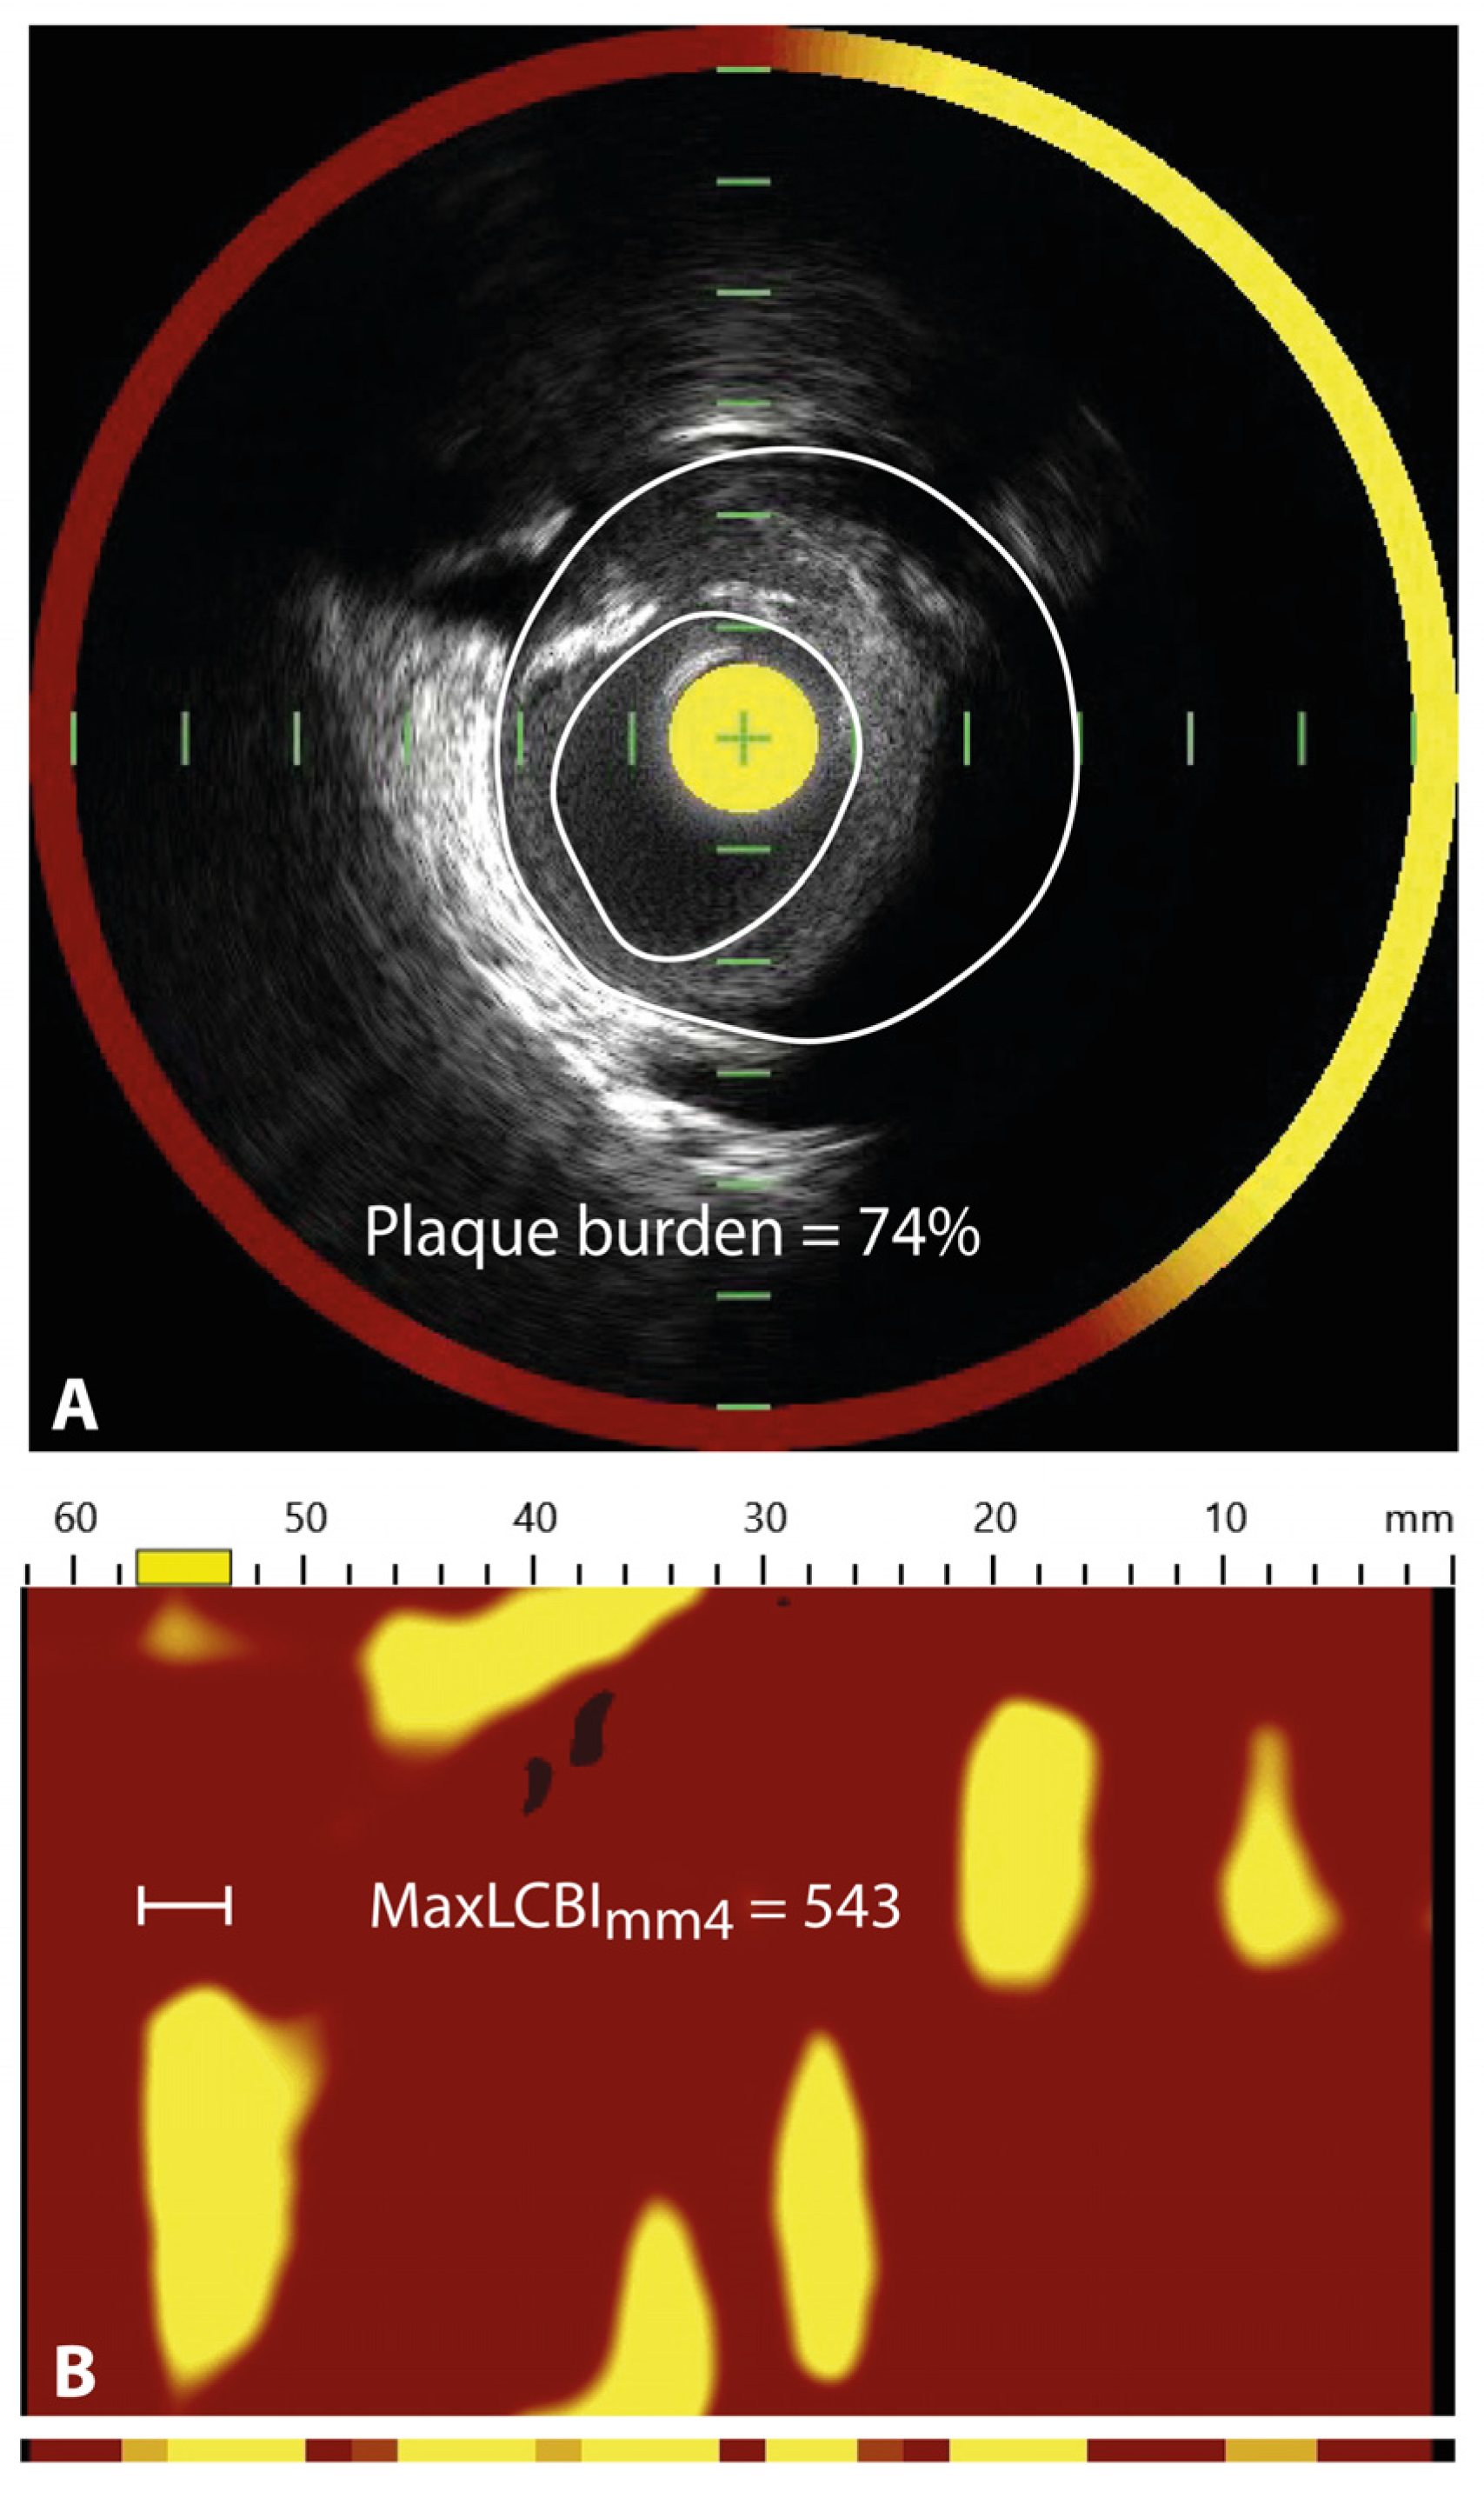

- Erlinge, D.; Maehara, A.; Ben-Yehuda, O.; Botker, H.E.; Maeng, M.; Kjoller-Hansen, L.; Engstrom, T.; Matsumura, M.; Crowley, A.; Dressler, O.; et al. Identification of vulnerable plaques and patients by intracoronary near-infrared spectroscopy and ultrasound (PROSPECT II): A prospective natural history study. Lancet 2021, 397, 985–995. [Google Scholar] [CrossRef]

- Puri, R.; Madder, R.D.; Madden, S.P.; Sum, S.T.; Wolski, K.; Muller, J.E.; Andrews, J.; King, K.L.; Kataoka, Y.; Uno, K.; et al. Near-Infrared Spectroscopy Enhances Intravascular Ultrasound Assessment of Vulnerable Coronary Plaque: A Combined Pathological and In Vivo Study. Arter. Thromb. Vasc. Biol. 2015, 35, 2423–2431. [Google Scholar] [CrossRef]

- Kang, S.J.; Mintz, G.S.; Pu, J.; Sum, S.T.; Madden, S.P.; Burke, A.P.; Xu, K.; Goldstein, J.A.; Stone, G.W.; Muller, J.E.; et al. Combined IVUS and NIRS detection of fibroatheromas: Histopathological validation in human coronary arteries. JACC Cardiovasc. Imaging 2015, 8, 184–194. [Google Scholar] [CrossRef]

- Waksman, R.; Di Mario, C.; Torguson, R.; Ali, Z.A.; Singh, V.; Skinner, W.H.; Artis, A.K.; Cate, T.T.; Powers, E.; Kim, C.; et al. Identification of patients and plaques vulnerable to future coronary events with near-infrared spectroscopy intravascular ultrasound imaging: A prospective, cohort study. Lancet 2019, 394, 1629–1637. [Google Scholar] [CrossRef]